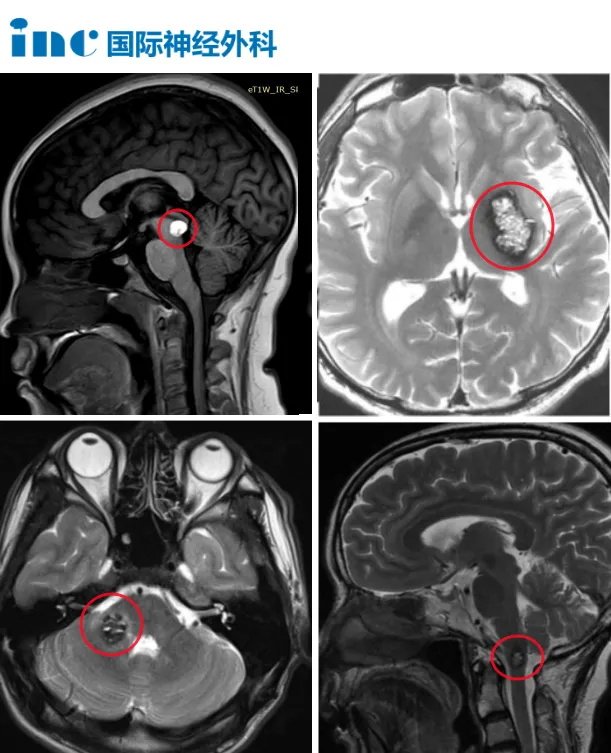

而等待示范手术的患者,或面临病情恶化的风险、或已经遭遇恶化的情况,且位于桥脑、延髓、中脑、基底节、岛叶等疑难位置,手术均面临着挑战。

▼部分示范手术患者术前影像